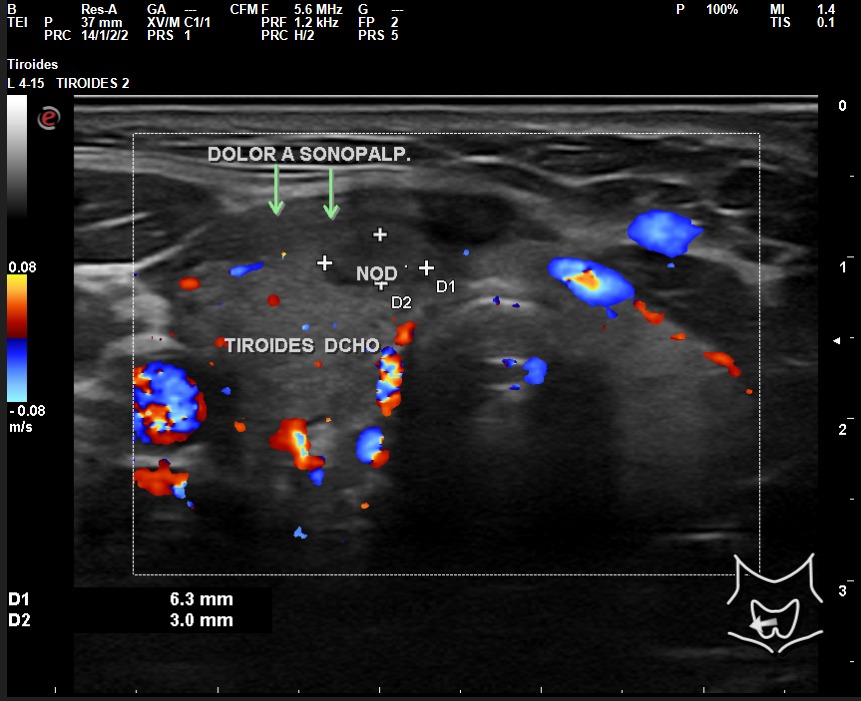

A la exploración ecográfica se observa en lóbulo tiroideo derecho áreas irregulares hipoecoicas sensibles a la sonopalpación con el transductor, con un ligero incremento de la actividad Doppler, asociado a la presencia de adenopatías de características reactivas y/o inflamatorias.

Los hallazgos ecográficos en otro contexto clínico, sin el dolor a la sonopalpación y sin el antecedente de posible viriasis previa, podrían ser muy parecidos al de un nódulo tiroideo sospechoso de malignidad: hipoecoico, márgenes irregulares, etc.